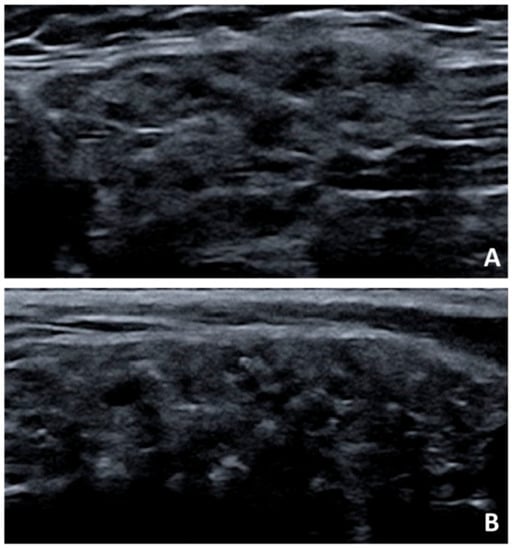

- Mossel, E.; Arends, S.; Van Nimwegen, J.F.; Delli, K.; Stel, A.J.; Kroese, F.G.M.; Spijkervet, F.K.L.; Vissink, A.; Bootsma, H. Scoring hypoechogenic areas in one parotid and one submandibular gland increases feasibility of ultrasound in primary Sjögren’s syndrome. Ann. Rheum. Dis. 2018, 77, 556–562. [Google Scholar] [CrossRef] [PubMed]

- Mossel, E.; Delli, K.; Arends, S.; Haacke, E.A.; Van Der Vegt, B.; Van Nimwegen, J.F.; Stel, A.J.; Spijkervet, F.K.L.; Vissink, A.; Kroese, F.G.M.; et al. Can ultrasound of the major salivary glands assess histopathological changes induced by treatment with rituximab in primary Sjögren’s syndrome? Ann. Rheum. Dis. 2019, 78, e27. [Google Scholar] [CrossRef]

- Cornec, D.; Jousse-Joulin, S.; Costa, S.; Marhadour, T.; Marcorelles, P.; Berthelot, J.M.; Hachulla, E.; Hatron, P.Y.; Goeb, V.; Vittecoq, O.; et al. High-grade salivary-gland involvement, assessed by histology or ultrasonography, is associated with a poor response to a single rituximab course in primary Sjögren’s syndrome: Data from the TEARS randomized trial. PLoS ONE 2016, 11, e0162787. [Google Scholar] [CrossRef]

- Theander, E.; Mandl, T. Primary Sjögren’s syndrome: Diagnostic and prognostic value of salivary gland ultrasonography using a simplified scoring system. Arthritis Care Res. 2014, 66, 1102–1107. [Google Scholar] [CrossRef]